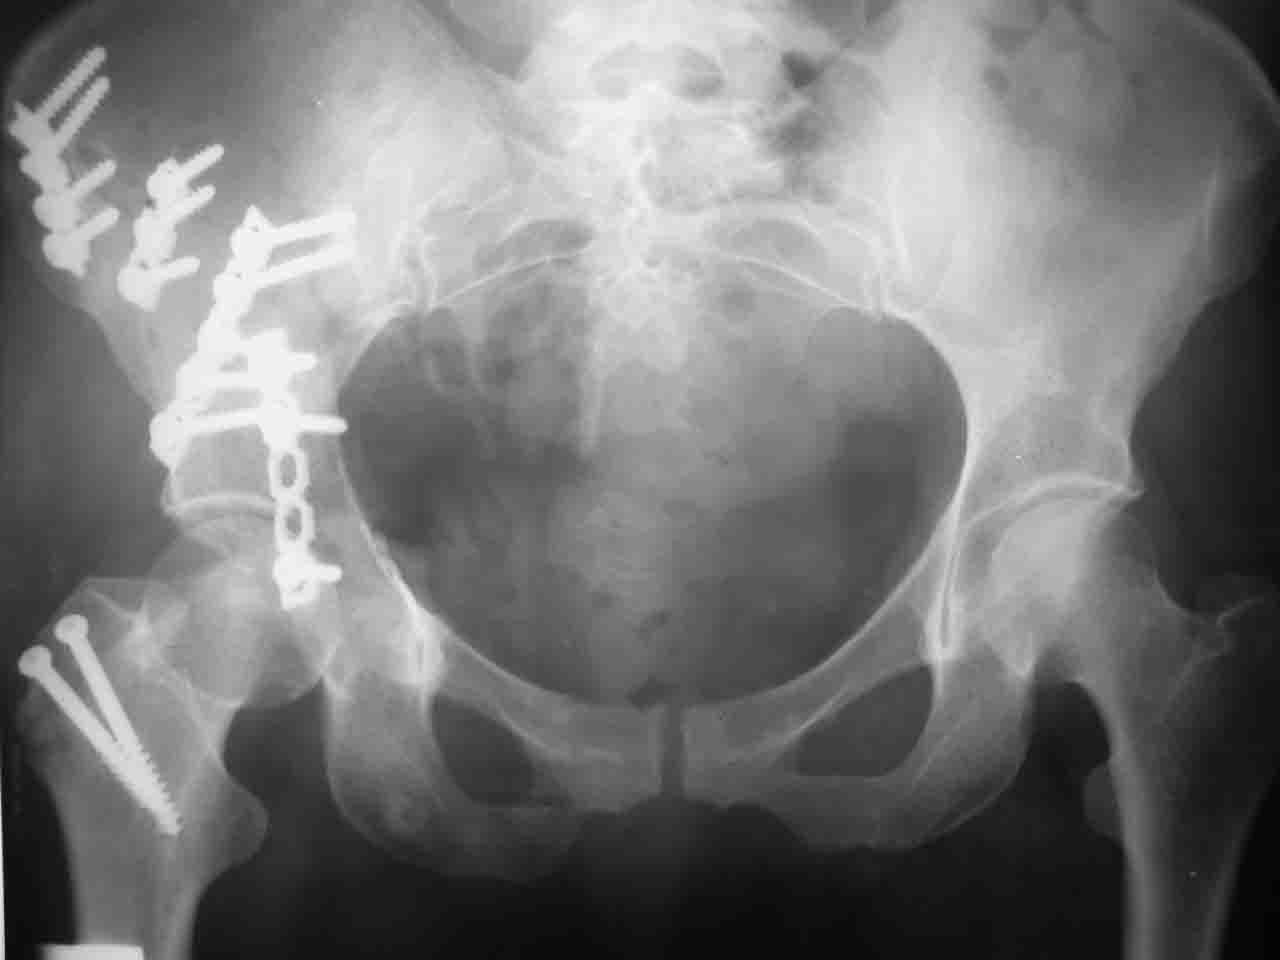

А какой отдел вертлужной впадины более важен передний или задний? Чем был обусловлен выбор доступа к суставу? Проще говоря, почему вы пошли передним доступом на двухколонный перелом? Мне понятны ваши сомнения, когда не удется сделать все что хотелось бы. В данном случае доступ должен быть чрезвертельным боковым (как и советовал Рунков) или двумя доступами.

Сложностью, ассоциативностью характера перелома, я бы с радостью воспользовался мининвазивной перкутанной фиксацией винтами, но боюсь, что результат был бы ещё хуже, техникой непрямой репозиции перелома не владею, поэтому пытаясь получить анатомичную впадину приходится широко открывать, по крайней мере пока, а дальше буду пытаться уменьшать пространство...

> передним доступом на двухколонный перелом?

Илеофеморальный доступ не совсем передний и сравнительно с илеоингвинальным, и Кохера-Лангенбека открывает весь наружный таз кроме самых передних отделов лонных костей, фиксацию которых я не ставил в задачу. Обширность диссекции, большая длительность операции и более высокий риск гетерооссификации - отрицательные моменты в обмен на возможность легче ориентироваться.

Комбинированные доступы - хорошая альтернатива, меньший процент осложнений, но я заметил , что без сбора *мозаики* безымянной кости сложно отрепонировать переднюю колонну, а с нерепонированной передней колонной невозможно анатомично собрать заднюю колонну и соотв. фрагменты стенки - так.что все равно открывать придется широко. Поэтому выбирая комбинированный

подход, передний доступ должен был бы быть продлен до задней трети крыла безымянной кости, а задний - практически до того же уровня, оставляя 6-7 см мостик. При этом вместо одного послеоп. рубца у больного остаются два сравнительно длинных.

Вопрос доступа к вертлужной впадине при остеосинтезе задача не простая. Конечно, у Летурнеля и Тайла всё давно описано, нам остается только брать на вооружение. Но сами понимаете, что не бывает двух одинаковых ситуаций, поэтому в каждом случае вопрос решается сугубо индивидуально. Наша главная цель - восстановить анатомию с нанесением минимальной дополнительной травмы тазобедреннному суставу, думаю с этим никто не поспорит. Расширенный илиофеморальный доступ уж слишком травматичен (как сказал один коллега "таз лежит отдельно, больной отдельно").Стоит ли делать из пациента анатомический препарат для того чтобы легче ориентироваться. Да и нужно ли собирать всю "мозаику"? Мы применяли при таких операциях своеобразную операционную хитрость - сначала устраняли грубое смещение крыла под гребнем с фиксацией так называемой "плавающей" пластиной (временно фиксированной на двух винтах)- доступ или продлевали боковой, или делали небольшой дополнительный разрез над гребнем. Это позволяло устранить грубое смещение и захождение отломков тела повздошной кости, что значительно облегчало репозицию и остеосинтез впадины над сводом. Основное внимание конечно же уделяли нагружаемому задне-верхнему отделу. Сообщите ваш адрес, пришлю схемы и рентгенограммы.